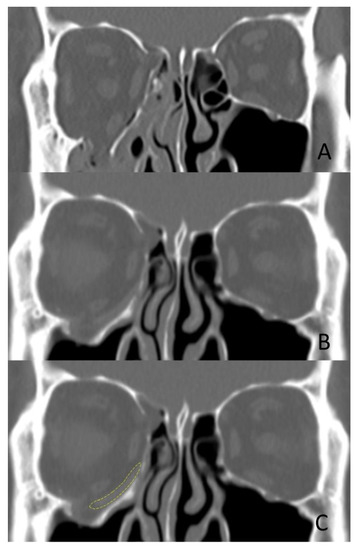

Inferomedial orbital fracture diagnoses were confirmed on CT or during surgery. Surgery was performed via a subciliary and transcaruncular approach as previously described [26]. In group A, the standardized 3D-printed implant was applied, while a hand-manipulated orbital implant composed of porous polyethylene was used in group B. To analyze the outcome, the symptoms were evaluated before and after surgery, and orbital volume was measured using CT at 3 days and 2 months after surgery (Figure 2).

Figure 2. CT of a patient with a 3D-printed standardized implant (group (A)) for a right orbital inferomedial fracture. (A) Preoperative CT. (B) At three months postoperative. (C) The implant outline is indicated by a yellow dotted line.